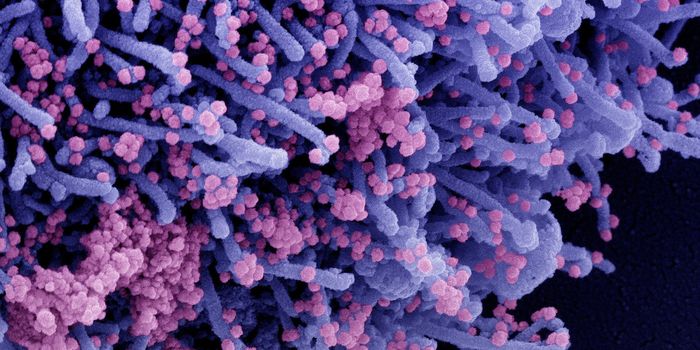

APR 04, 2022Cell & Molecular BiologyAbout 1.5 million new HIV infections are thought to have occurred last year, and while COVID-19 has dominated concerns a ...